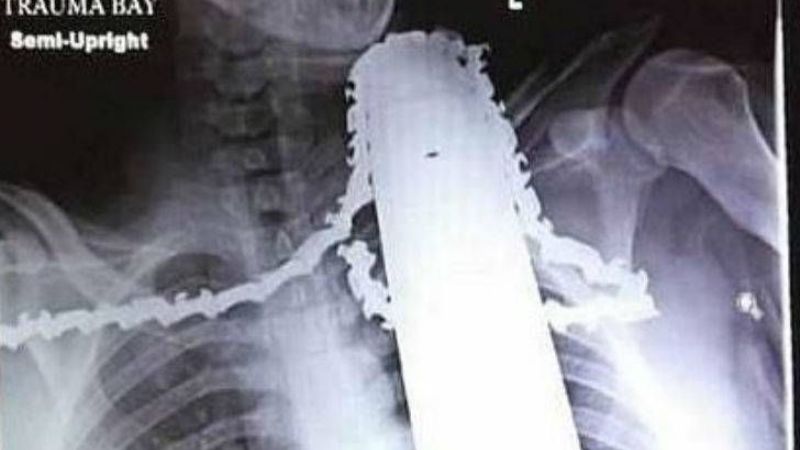

Una motosierra le perforó el cuello y sobrevivió

La filosa hoja quedó a un centímetro de la arteria carótida. Está estable.

En medio de la desgracia, la suerte le hizo un guiño y le regaló un renacer a James Valentine, quien estuvo a punto de perder la vida cuando la motosierra que manipulaba se le clavó hasta el cuello. Con la radiografía como testimonio del milagro, el afortunado aún no puede creer que la filosa hoja se haya detenido a solo un centímetro de la arteria carótida.

Este trabajador de 21 años estaba podando un pino en la ciudad de Ross Township, Estados Unidos, cuando perdió el control de la motosierra y se la clavó en el pecho deslizándose peligrosamente hasta su cuello.

Sus compañeros de una empresa de mantenimiento de árboles en Pittsburgh reaccionaron rápidamente desactivando el aparato, pero le dejaron la hoja en el cuerpo y así lo llevaron al hospital.

Los médicos quedaron estupefactos puesto que la motosierra no dañó la médula espinal, el esófago ni las vías respiratorias. Sólo afectó músculos y tejido el hombro.